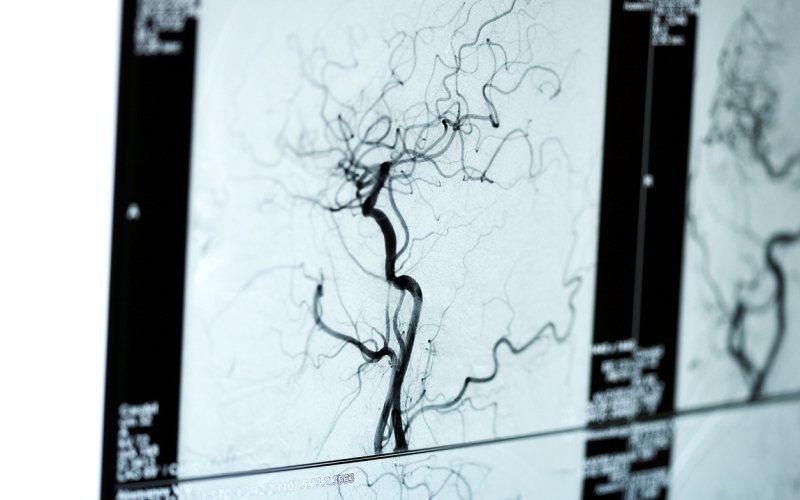

Corrección de arritmias por estudio electrofisiológico

Esta técnica localiza estas anomalías cardiacas mediante cateterismo y las repara sin cirugía

Las arritmias son alteraciones en el ritmo cardiaco que, dependiendo de los casos, tienen mayor o menor gravedad pudiendo llegar en situaciones extremas a provocar la muerte. Sin llegar a este punto, lo cierto es que los propios síntomas q...